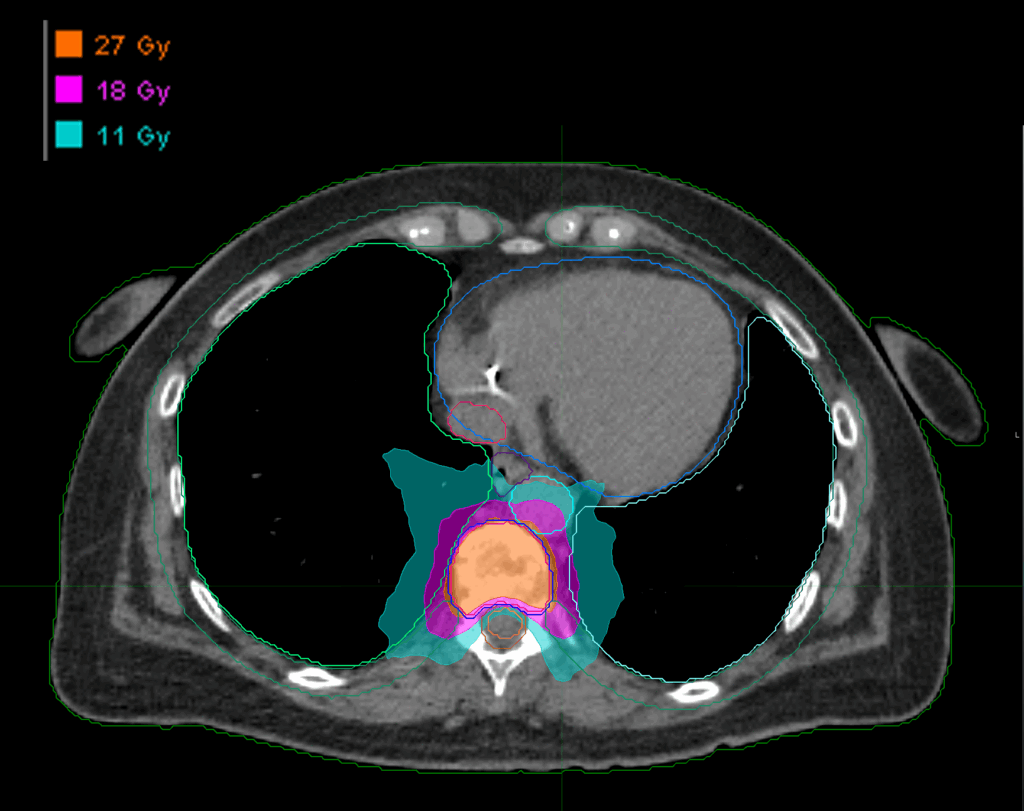

Treatment Plan Images

Fractionation

27 Gy in 3 fractions

Dose Distributions

- Prescription to the

75.6% isodose line - Max. dose 35.71 Gy